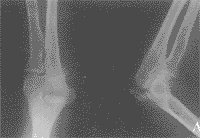

本组全部获随访,时间8~39月,平均24月。平均骨折愈合时间为7周,未发生骨折端再移位(封三附图)。两组疗效比较无显著性差异(P<0.05),见表2。

附图 尺骨鹰嘴骨折手术前(A)与手术后(B)X线正侧位片表现